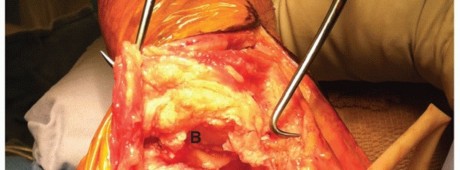

The muscular interval is developed distally down to the insertion of the deltoid into the deltoid tuberosity and the insertion of the pectoralis major into the lateral lip of the bicipital groove (FIG 4D,E).

To expose the bone fully, the surgeon may need to detach part or all of the insertion of pectoralis major muscle.

The minimum amount of soft tissue should be detached to allow adequate visualization and reduction of the fracture.

If further exposure is needed, the surgeon dissects medially in a subperiosteal manner to avoid damage to the radial nerve, which lies in the spiral groove of the humerus and crosses the back of the middle third of the bone in a medial to lateral direction.